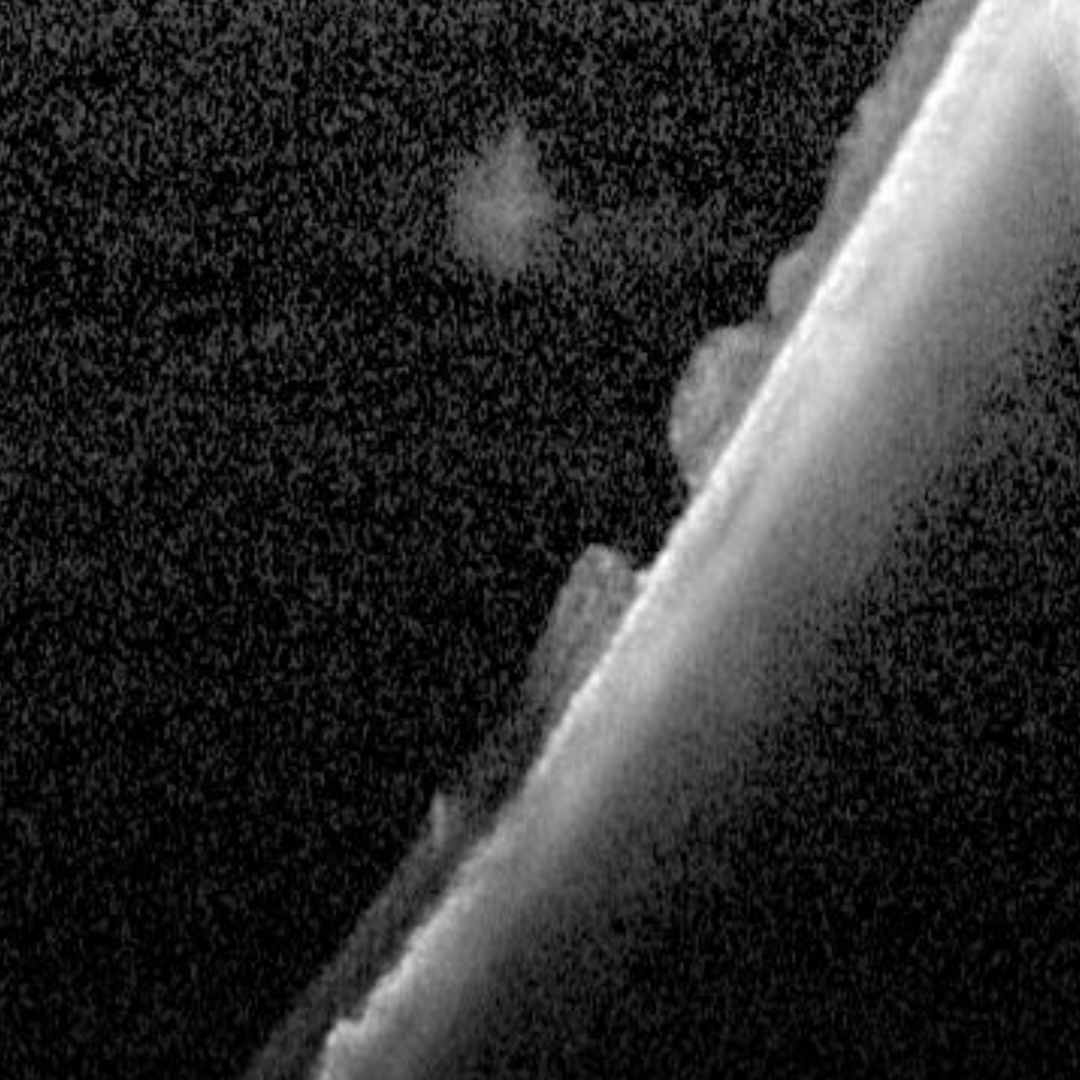

OCT shows a full thickness retinal break with the operculum often visible in the vitreous overlying the hole. The retinal hole may have subretinal fluid adjacent.

Case 3: Operculated hole

An asymptomatic 66-year-old Asian male with best corrected visual acuity in the left eye of 6/6 (20/20).